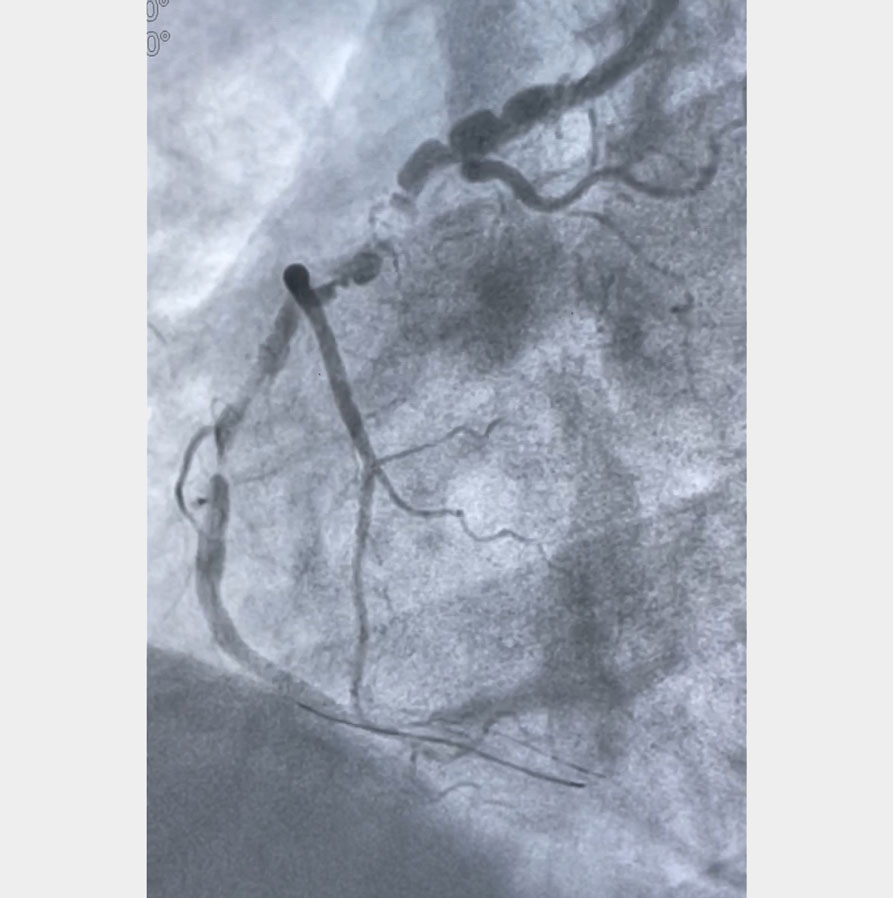

A long winding road